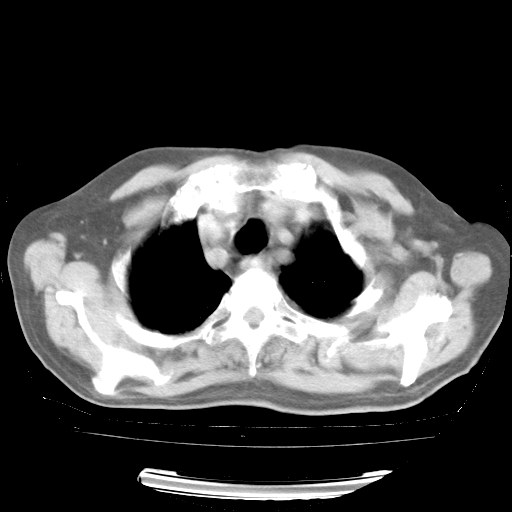

4月28日肺部CT——再次出现类似去年5月9日——透光度降低,“间质性”改变。

4月28日肺部CT——再次出现类似去年5月9日——磨玻璃样、间有“粟粒样”改变。

4月28日肺部CT